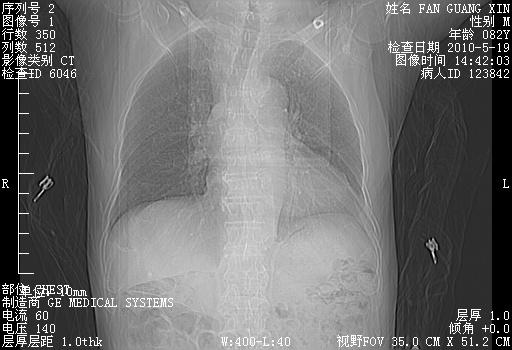

复查肺部CT,明显好转。为什么发热呢?

治疗3周后的肺部CT

治疗3周后的肺部CT纵隔窗